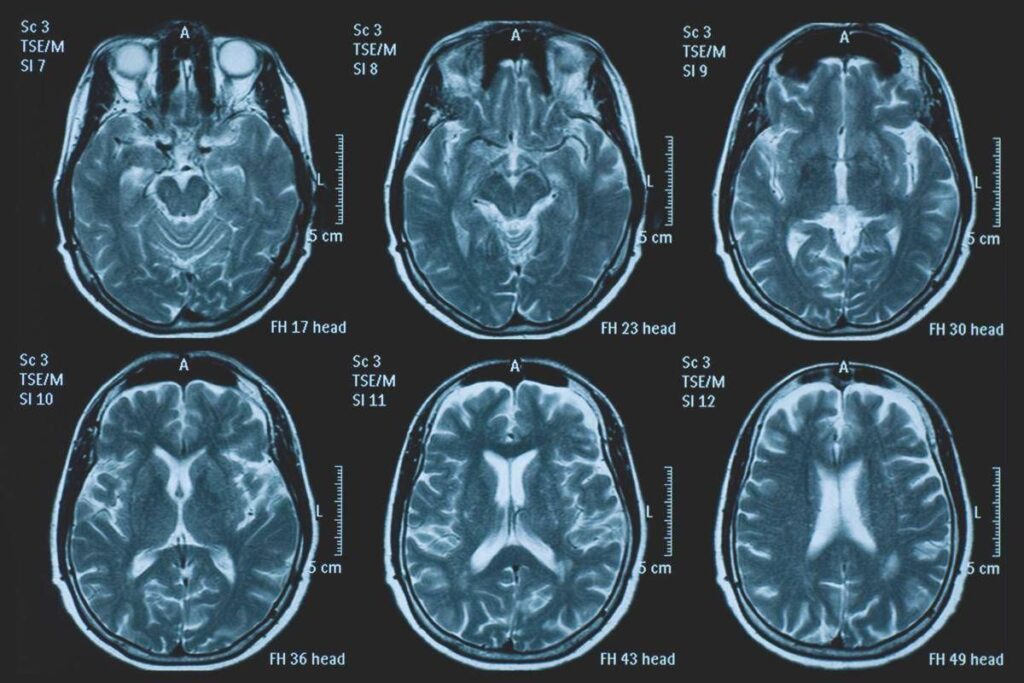

(Adnkronos) – La Commissione europea (Ce) ha autorizzato la commercializzazione condizionata di tovorafenib come monoterapia per il trattamento dei pazienti di età pari o superiore a 6 mesi con glioma pediatrico di basso grado che presentano una fusione o un riarrangiamento del gene Braf o una mutazione Braf-V600, in progressione di malattia dopo una o più terapie sistemiche precedenti. Lo annuncia Ipsen, in una nota, precisando che si tratta della “prima terapia mirata” per questa patologia e che la decisione della Ce si riferisce ai 27 Stati membri della Ue, oltre a Islanda, Liechtenstein e Norvegia. Ogni anno in Ue vengono diagnosticati più di 800 nuovi casi di glioma pediatrico di basso grado (pLgg) con alterazione di Braf. Questo tumore cerebrale, nonostante sia classificato di basso grado (a lenta progressione), comporta un carico significativo e permanente che accompagna la persona per tutta la vita, causando spesso importanti compromissioni fisiche e neurologiche, tra cui perdita della vista, difficoltà di linguaggio e disfunzioni motorie, che possono incidere in modo significativo sull’istruzione, l’autonomia e la qualità di vita a lungo termine del bambino. Finora, molti bambini con pLgg hanno dovuto sottoporsi a interventi chirurgici invasivi, a più cicli di chemioterapia e a radioterapia, con conseguenti complicazioni della salute.